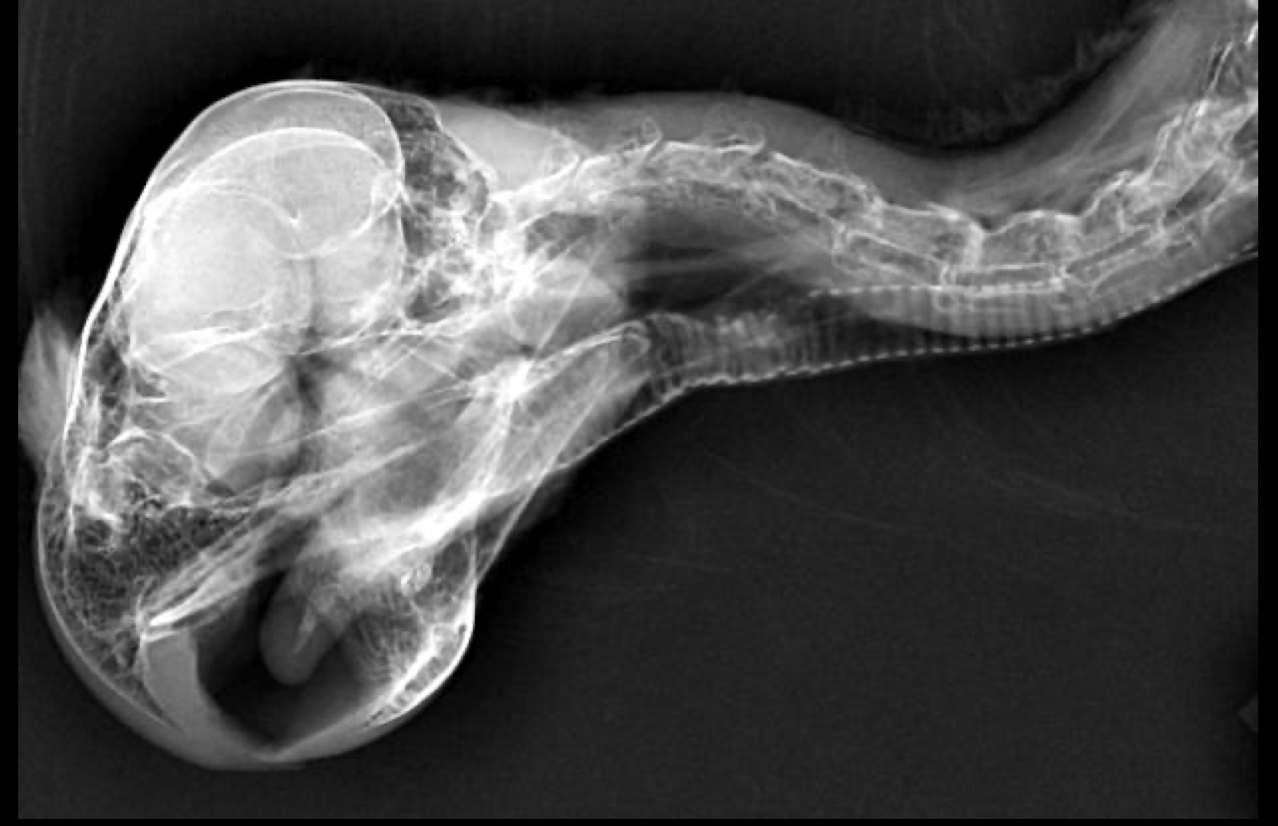

Normal avian skull xray